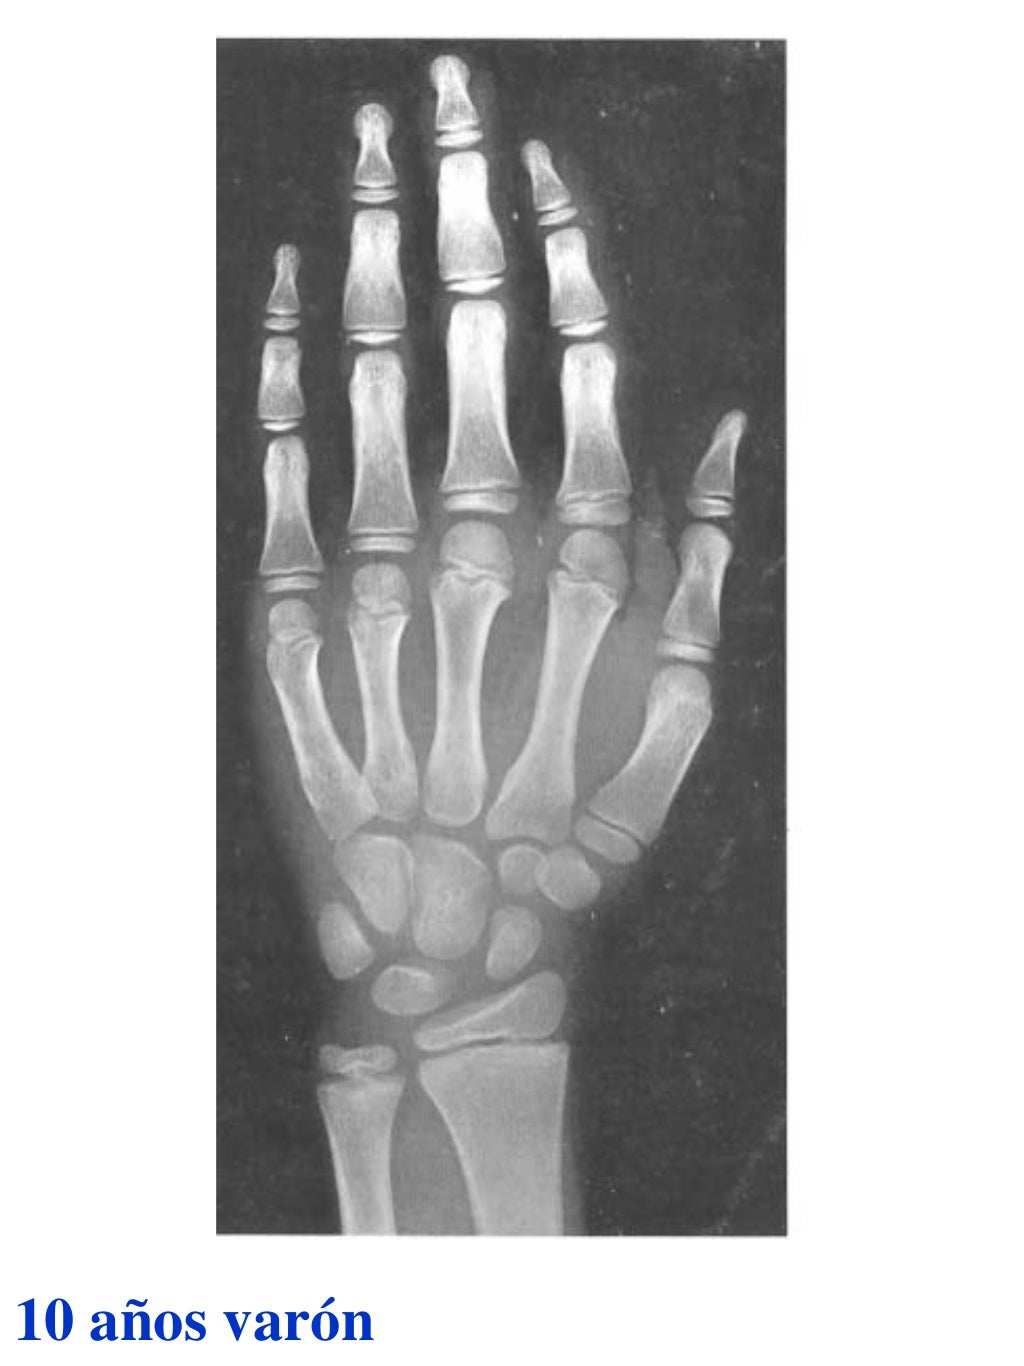

Tablas De Greulich Y Pyle The standards established by greulich and pyle, undoubtedly the most popular method, consist of two series of standard plates. The standards established by greulich and pyle, undoubtedly the most popular method, consist of two series of standard plates. El documento lista las edades. This systematic review summarizes the. The greulich and pyle method is one of the two main ways to assess the bone age of children. Both main methods of bone age. Scribd is the world's largest social reading and publishing site. 153 recomendaciones • 616,869 vistas. Atlas greulich y pyle | pdf | descarga gratuita. The greulich and pyle atlas is used to estimate the age of children and adolescents. The radiographic atlas of skeletal development of the hand and wrist by ww greulich and si pyle is a classic radiological.

Tablas De Greulich Y Pyle . Scribd is the world's largest social reading and publishing site. This systematic review summarizes the. The radiographic atlas of skeletal development of the hand and wrist by ww greulich and si pyle is a classic radiological. The standards established by greulich and pyle, undoubtedly the most popular method, consist of two series of standard plates. The greulich and pyle method is one of the two main ways to assess the bone age of children. El documento lista las edades. Both main methods of bone age. 153 recomendaciones • 616,869 vistas. Atlas greulich y pyle | pdf | descarga gratuita. The greulich and pyle atlas is used to estimate the age of children and adolescents.